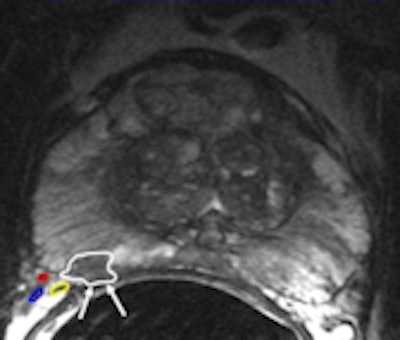

A 48-year-old sexually active male with PSA 9; TRUS biopsy Gleason 4+3 PC at right PZ; stage T1c. Nerve-sparing prostatectomy was performed showing submillimeter ECE and negative resection margins. Postsurgery patient was potent and continent. Left: Axial T2-weighted MR image shows low signal tumor in right PZ (white area) with obliteration of the white fat at the rectoprostatic angle (arrows), indicating minimal ECE = PI-RADS 5. The NVB is indicated by red, blue, and yellow. Right: Nerve-sparing prostatectomy showed Gleason 4+3 PC with submillimeter ECE (T; blue area) at right PZ. Resection margins were negative. Patient was potent after surgery.One in six men in their lifetime will be clinically diagnosed with prostate cancer, and this accounts for 350,000 cases, annually or 25% of all new male malignancies diagnosed in Europe, the authors noted. Currently, digital rectal examination, serum prostate specific antigen (PSA) -- a nonspecific blood test -- and transrectal ultrasound-guided biopsy -- where the target is mostly invisible -- are used as diagnostic tools.